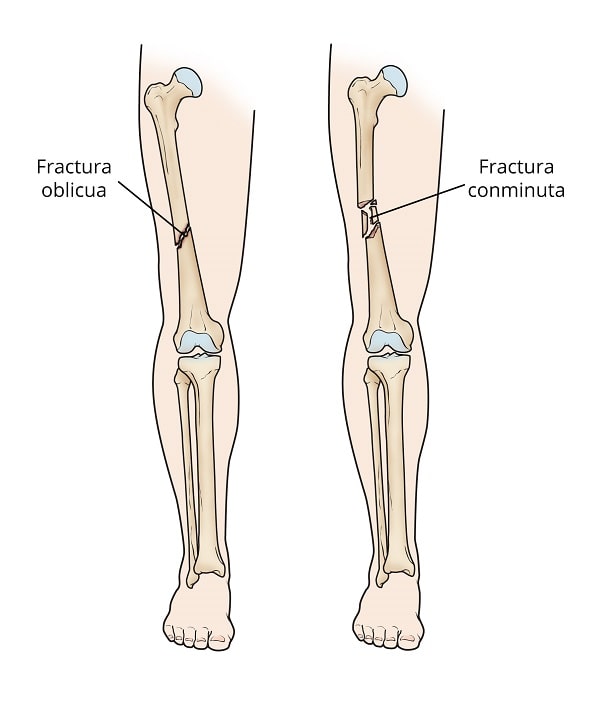

Fractura oblicua. Este tipo de fractura tiene una línea angular a lo largo de la diáfisis.

Fractura conminuta. En este tipo de fractura, el hueso se rompe en tres o más partes. En la mayoría de los casos, la cantidad de fragmentos de hueso coincide con la intensidad de fuerza necesaria para romper el hueso.

(Izquierda) Una fractura oblicua con una línea angular a través de la diáfisis. (Derecha) En una fractura conminuta, el hueso se rompe en tres partes o más.